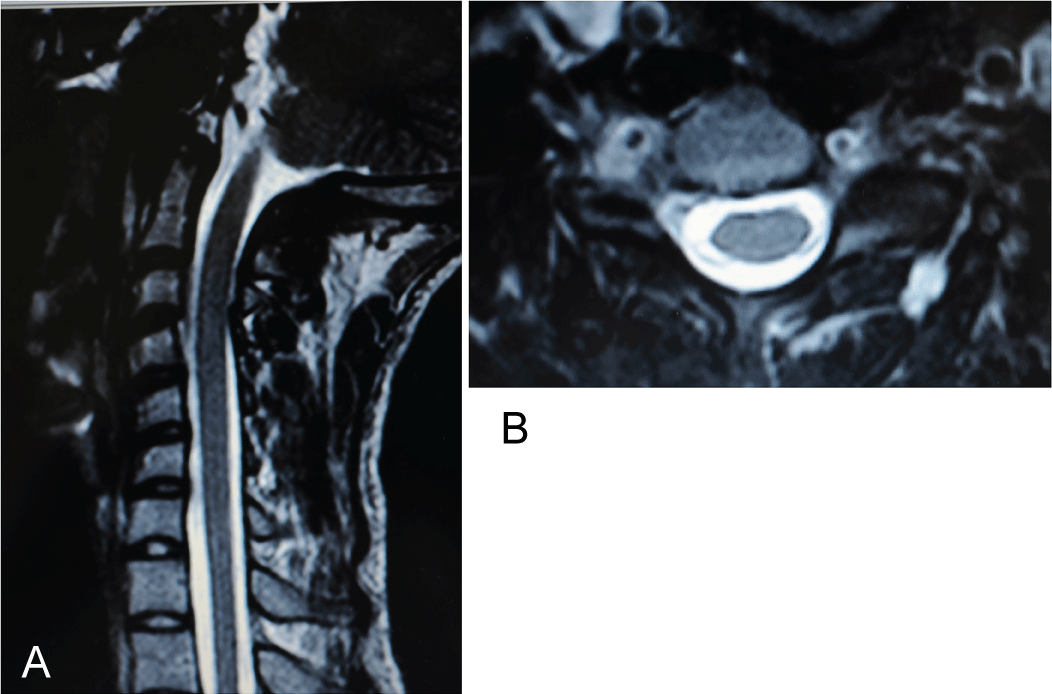

This patient study was approved by the Ethics Committee and was conducted following completion of the corresponding informed consent. A 10-year-old male patient in 2008 had consulted for a torticollis deformity that had originated during early childhood. This delay in first diagnosis is because patient is inmigrant and without diagnosis or previous treatment. Patient had classical deformities of torticollis: Shortening of SCM muscle, lateral inclination of the neck, smaller and higher eye, contralateral torsion with chin rising. Moreover, the patient also presented with a left-side facial deformity. The patient was not referred for any traumatic or infectious etiology of the oropharynx or for digestive or renal diseases. It was made a wide differential diagnosis, especially for to exclude nonmuscular causes of torticollis, presents in 18% of patients [1], Klippel-Feil anomalies (30%), posterior fossa tumors, syringomyelia or Arnold-Chiari malformation (51%) [1,2]. Additionally, neurologic exploration was done by a pediatric neurologist. Problems like dystonia, ataxia or abnormal deep tendon reflexes in upper and lower limbs did not exist. Also, osteocongenital neurological pathologies of the spinal cord and brain tumor were excluded by a pediatric neurologist. After these exclusions were made, we confirmed a diagnosis of inveterate congenital muscular torticollis. Preoperative studies, radiographic imaging, Computed Axial Tomography (CT) scans and Magnetic Resonance Imaging (MRI) of the cervical spine and skull (Figure1a, Figure 1b, Figure 2a, Figure 2b, Figure 3a, Figure 3b, Figure 4a, Figure 4b) highlighted Klippel-Feil Syndrome, fusion defects of the vertebral arches of the atlas, diastematomyelia and hypoplasia of the occipital condyles. CT images demonstrated, deformity of the anterior arch of the atlas was observed, consisting of hypoplasia of the right half and deformity and hypoplasia of the posterior arches C1 and C2 with concavity of the right posterior hemi-arch and convexity of the left arch, causing asymmetry of the spinal canal. Additionally, subluxation of the odontoid apophysis toward a right lateral mass of the atlas was observed (Figure 2a, Figure 3a). MRI showed deformity with extreme narrowing of the odontoid apophysis and irregular formation of the spinal canal with displacement of the spinal cord in the direction of the concavity of the torticollis (Figure 4a, Figure 4b). In 2009, unipolar distal tenotomy of the left SCM was performed, followed by orthotics and rehabilitation with notable improvement in cervical mobility but with minimal effect on facial asymmetry. In the 5-year postoperative CT and MRI, there were no significant changes in preoperative vertebral bone deformities, either visually or through the morphology of the spinal canal (Figure 5a, Figure 5b, and Figure 6).

Figure 4: MR-scanning: a) Sagittal plane: A normal spinal cord in the cervical spinal canal; b) Axial plane: Spinal canal asymmetry was marked by a displaced spinal cord to the left (i.e., toward the concavity of the torticollis). View Figure 4